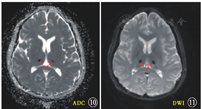

MRI检查丘脑等灰白质病变区,初期出现T1强化像低信号,T2强化像高信号。数日后病变内部,无论是T1还是T2像,均出现高信号。脑白质病变始终T1呈低信号,T2呈高信号。慢性期丘脑病变缩小或消失,白质病变囊性化或消失。1例ANE患者丘脑的MRI动态变化见图1,图2,图3,图4,图5,图6[22] 。

注:T1WI:T1加权成像;T2WI:T2加权成像;FLAIR:液体衰减反转恢复